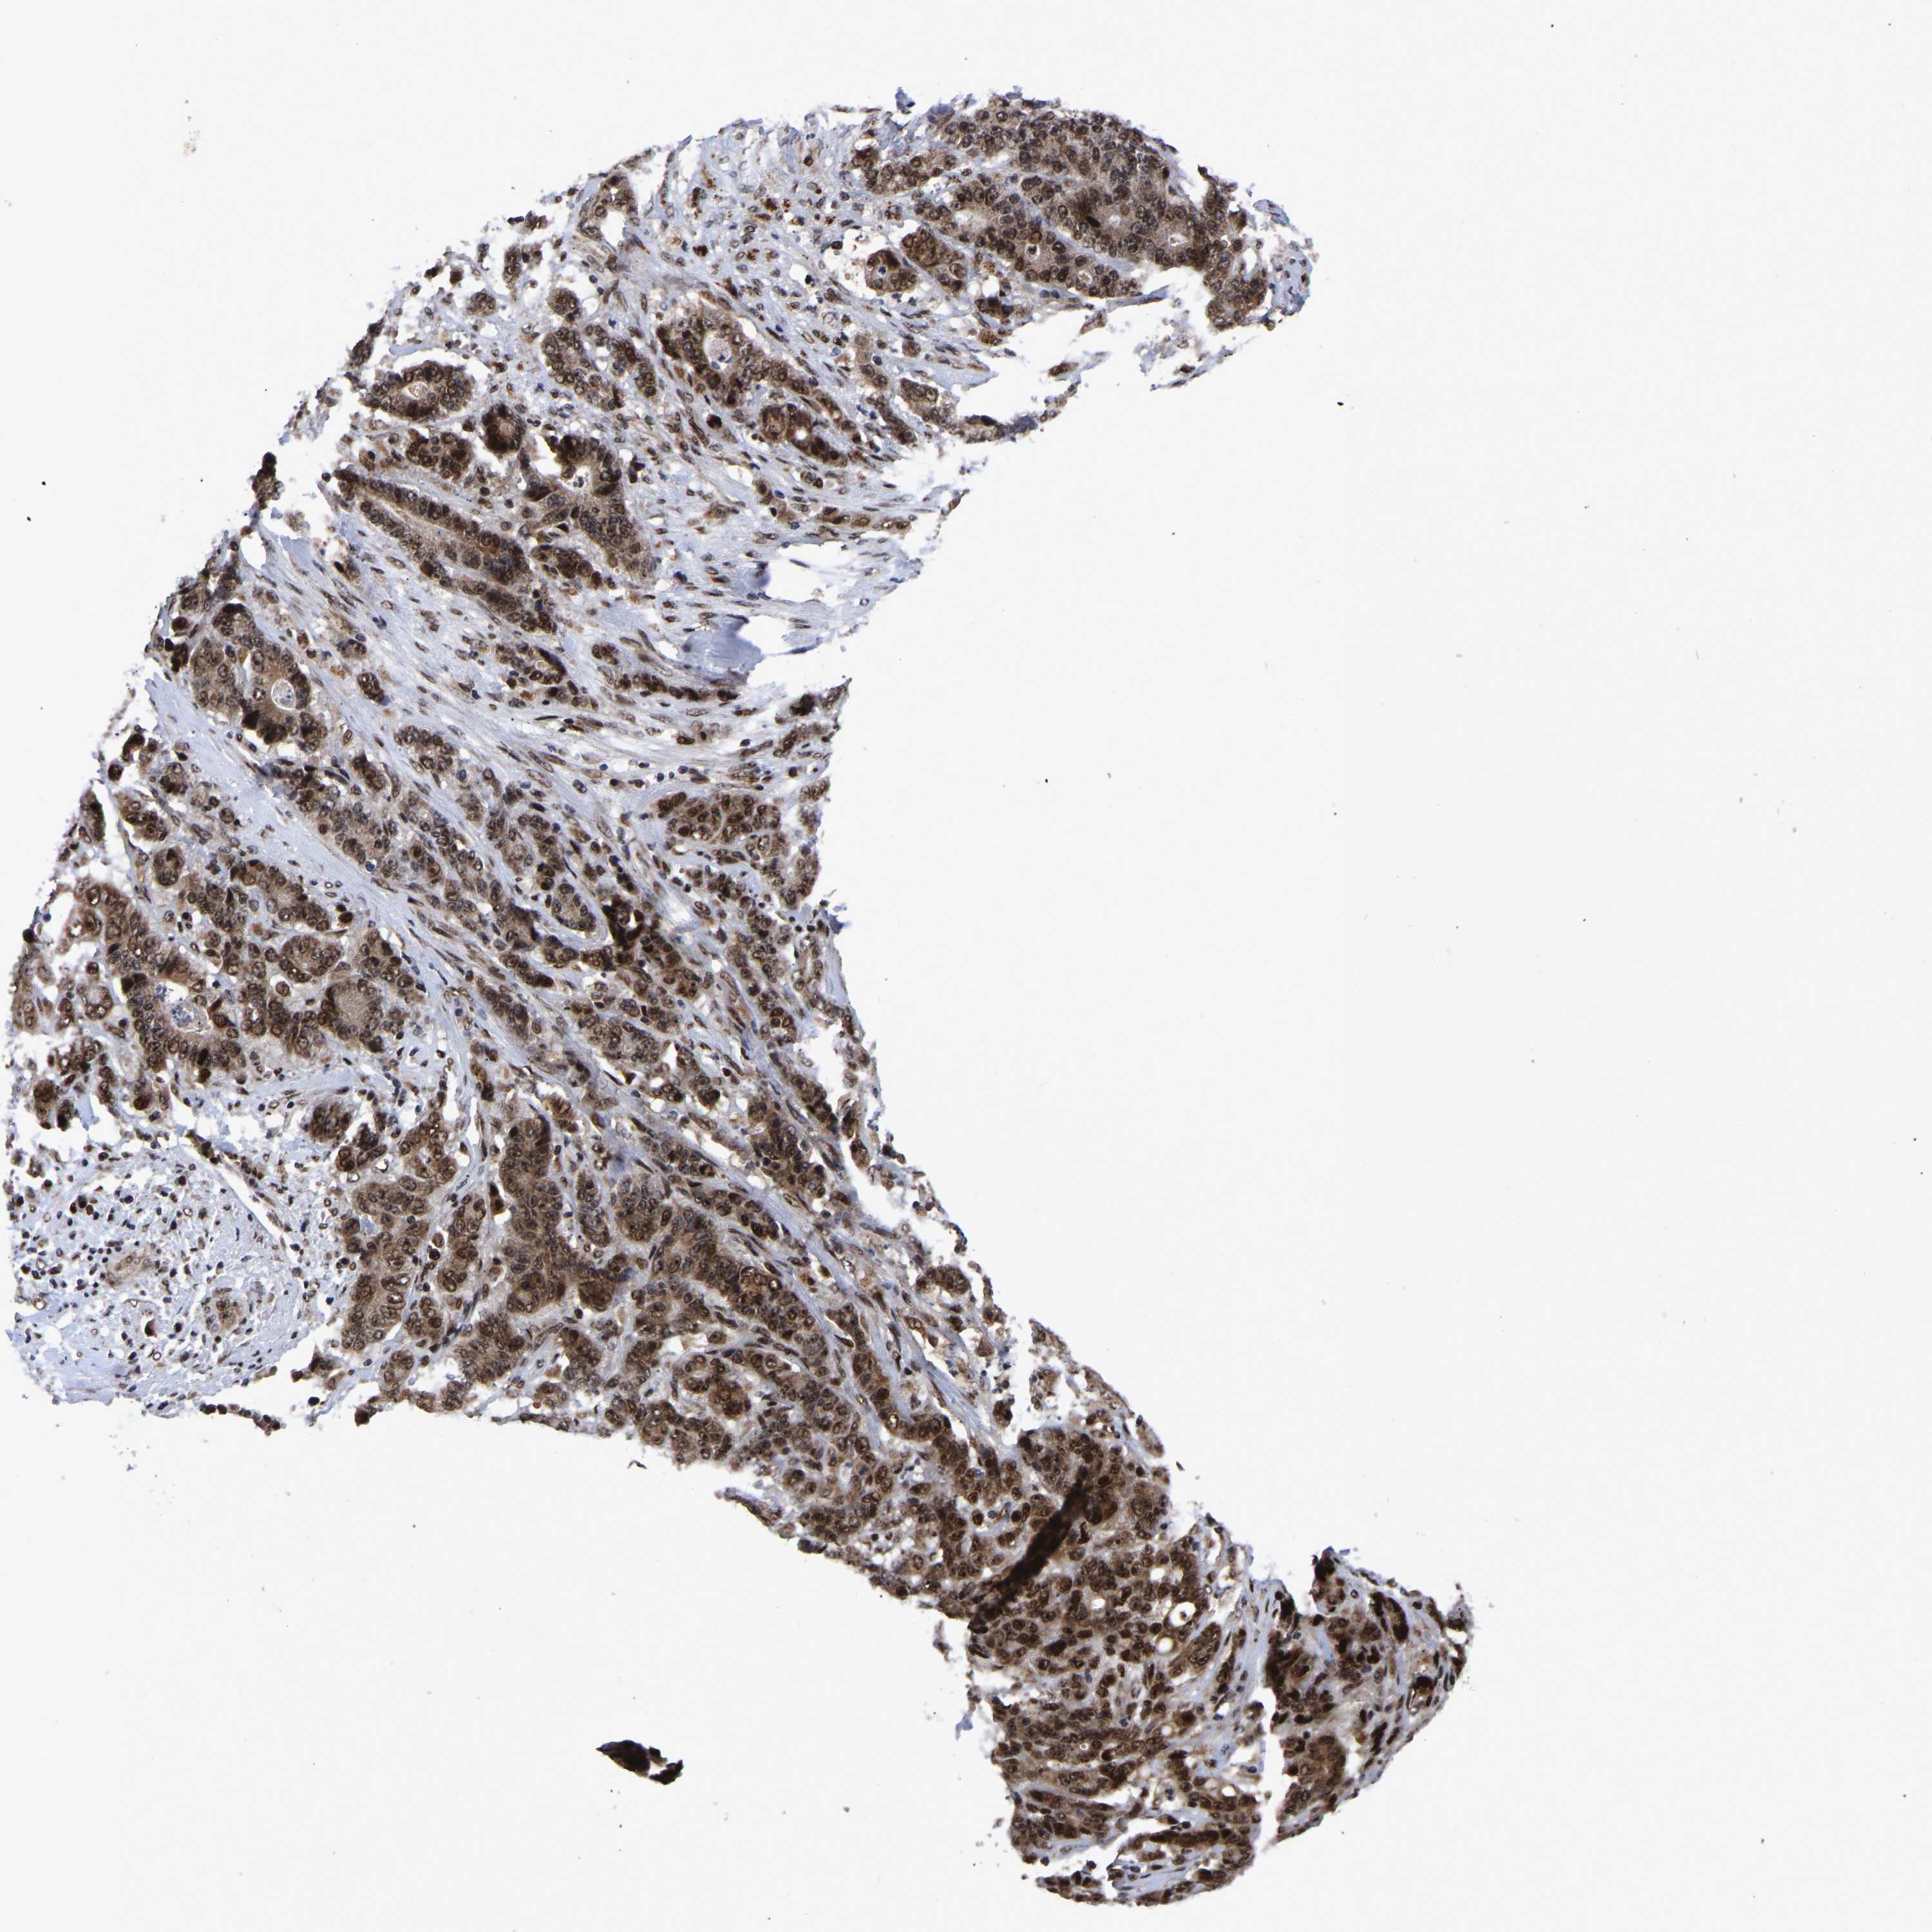

STOMACH CANCER - Protein expressioni

A mouse-over function shows sample information and annotation data. Click on an image to view it in a full screen mode. Samples can be filtered based on level of antibody staining by selecting one or several of the following categories: high, medium, low and not detected. The assay and annotation is described here.

Note that samples used for immunohistochemistry by the Human Protein Atlas do not correspond to samples in the TCGA dataset.

Antibody stainingi

Antibody staining in the annotated cell types in the current human tissue is reported as not detected, low, medium, or high, based on conventional immunohistochemistry profiling in selected tissues. This score is based on the combination of the staining intensity and fraction of stained cells.

Each image is clickable and will lead to virtual microscopy that enables deeper exploration of all samples and also displays staining intensity scores, fraction scores and subcellular localization as well as patient and tissue information for each sample.

Antibody HPA019149

Antibody CAB004464

Staining

High

Medium

Low

Not detected

Intensity

Strong

Moderate

Weak

Negative

Quantity

>75%

75%-25%

<25%

None

Location

Nuclear

Cytoplasmic/membranous

Cytoplasmic/membranous,nuclear

Adenocarcinoma, NOS

Adenocarcinoma, High grade